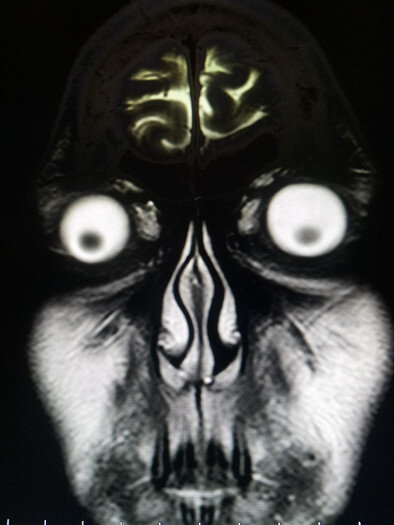

Кому-то действительно хотелось увидеть снимок головы . Наверное, всё же не стоило.